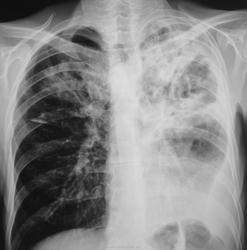

Через 8 месяцев пациент "простыл" и был направлен терапевтом на "флюшку" по поводу пневмонии, почему, именно, на флюорографию, ибо, состоит на учете у фтизиатра, совсем не понятно.

Коллеги, вместе с фтизиатром решили пролечить пневмонию в условиях отделения общего профиля.

Лечили интенсивно две недели. Итог лечения ниже.

Пацент направлен в облтуббольницу.